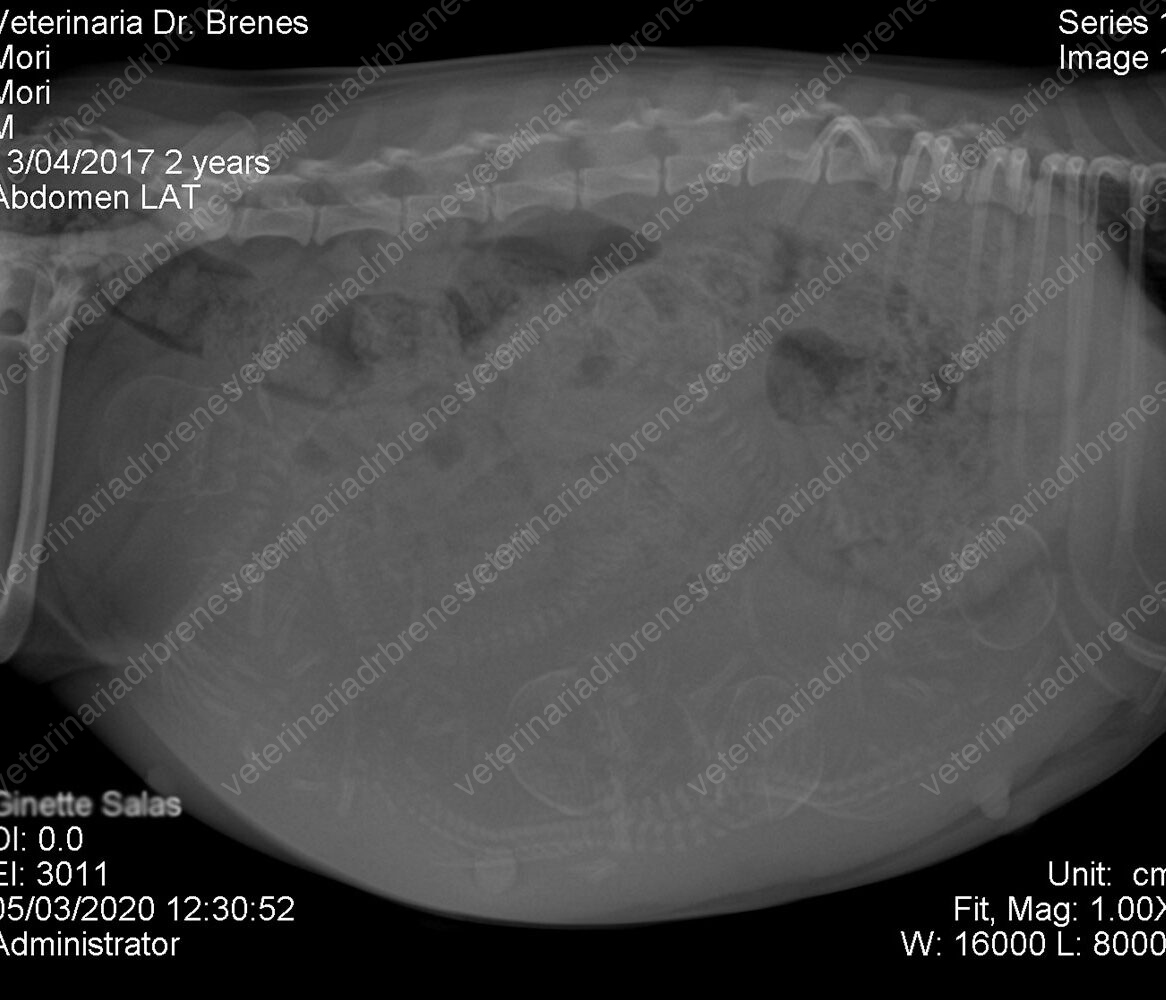

Los estudios radiológicos son métodos complementarios no invasivos que nos ayudan a valorar a nuestros pacientes. Los Rayos X los utilizamos para poder observar la integridad de los huesos en caso de sospecha de fracturas. Modificando la técnica radiológica podemos observar estructuras blandas como ciertos órganos: corazón, pulmón, hígado, bazo, vejiga, riñones etc. Cuando sospechamos de cuerpos extraños en el estómago o intestino, se realizan radiografías con medio de contraste, el cual nos permitir visualizar el pasaje intestinal, así como cuerpos extraños que retenga el medio de contraste como por ejemplo telas, papel u otros materiales que puedan contener el medio de contraste.